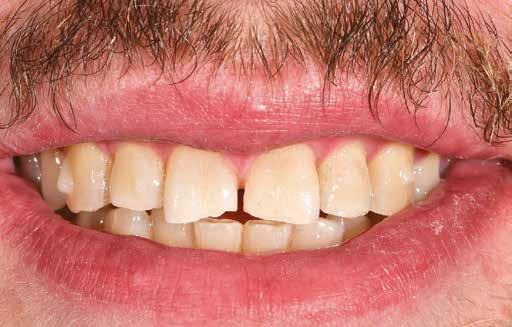

A 26 éves férfi páciens azzal a kéréssel kereste fel a rendelőnket, hogy a frontfogai esztétikusabb megjelenését szeretné elérni. A páciens jó általános egészségi állapottal rendelkezett, nem szenvedett allergiáktól és nem kellett rendszeresen gyógyszereket szednie. A páciens lehetőség szerint kerülte a fogai megmutatását. Rendkívül zavarónak találta a nagymetszői között, a középvonalnak megfelelően látható rést, a fogain látható kopási jeleket, valamint a fogai méretét is túl kicsinek találta. A szájüregi vizsgálat során megállapítottuk, hogy a nagymetsző fogai (11, 21) élharapásban vannak, valamint az alsó fogíven kismértékű torlódást észleltünk. A felső frontfogakon

(13-23) attrícióra utaló jeleket találtunk. A fogak kopása a nagymetszőfogaknak megfelelően volt a legkifejezettebb (1. ábra) . Az előbbiekben említett fogak (11, 21) ezen kívül némileg elfordultak, és jelentősebb méretű diasztéma volt köztük. A páciens Angle I.-osztályú állcsontrelációs helyzettel rendelkezett. A vizsgálat során feltűnt, hogy a páciens csak nagyon óvatosan mert mosolyogni (2. ábra)

A fogazat minimálinvazív módon készített héjakkal történő ellátásához a fogaknak olyan pozícióban kell lenniük, amely lehetővé teszi az esztétikai megjelenés additív eljárások alkalmazása mellett történő optimalizálását.1. ábra: Kiindulási állapot. A felső nagymetszőfogak élharapásban vannak. 2. ábra: Az orthodonciai kezelés megkezdése előtt készített intraorális felvétel. A páciens csak óvatosan mer mosolyogni. 3. és 4. ábra: Digitálisan megtervezett kezelés.